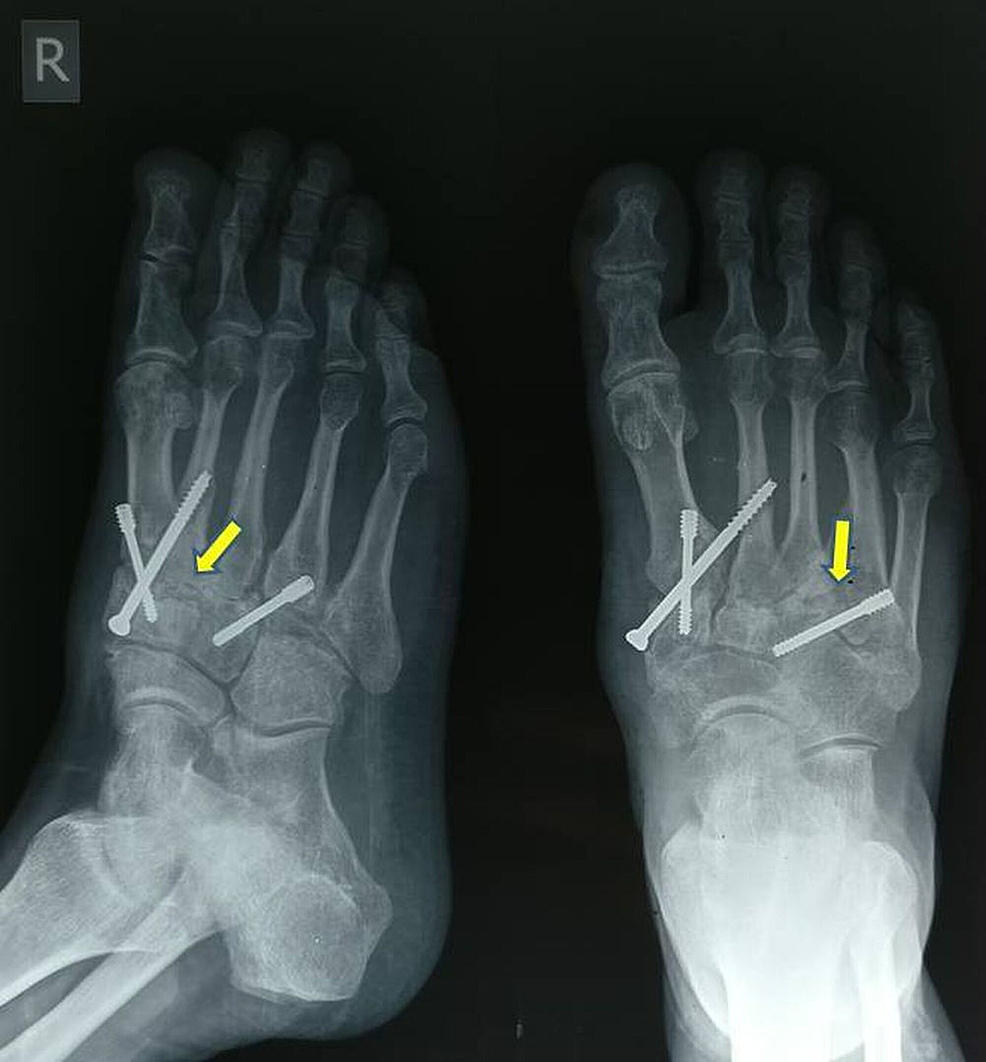

From www.cureus.com

Cureus Posttraumatic Arthritis of the Tarsometatarsal Joint Complex What Are Tmt Joints The tarsometatarsal joints (lisfranc's) are arthrodial joints. Some authors combine the medial and middle columns into the medial column as the three tarsometatarsal (tmt) joints are relatively immobile. The bones entering into their formation are the first, second, and third cuneiforms, and the cuboid, which articulate with. Midfoot arthritis is joint pain and inflammation that impacts the bones that make. What Are Tmt Joints.

Cureus Posttraumatic Arthritis of the Tarsometatarsal Joint Complex What Are Tmt Joints Articulationes tarsometatarsales) are three synovial plane type joints located in the foot. Some authors combine the medial and middle columns into the medial column as the three tarsometatarsal (tmt) joints are relatively immobile. The tarsometatarsal joints (lisfranc's) are arthrodial joints. The bones entering into their formation are the first, second, and third cuneiforms, and the cuboid, which articulate with. These. What Are Tmt Joints.